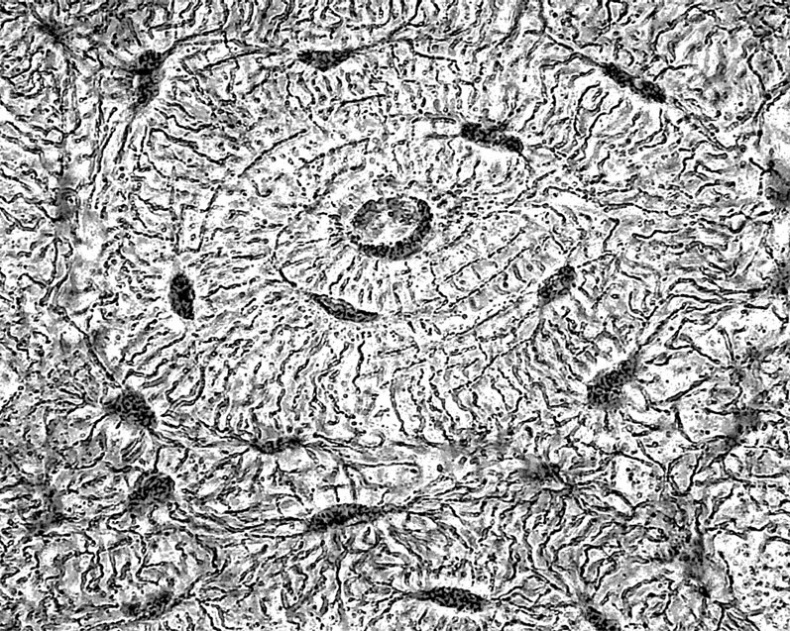

Мерцательный эпителий

Кроме перечисленных функций, эпителиальная ткань может участвовать во всасывании веществ (эпителий кишечника) и в газообмене (эпителий легких). Дыхательные пути выстланы особым видом эпителиальной ткани, называемой «мерцательным эпителием», клетки которого имеют обращенные наружу подвижные реснички. Эти реснички удаляют из дыхательных путей мелкие твердые частицы, попадающие туда с воздухом.